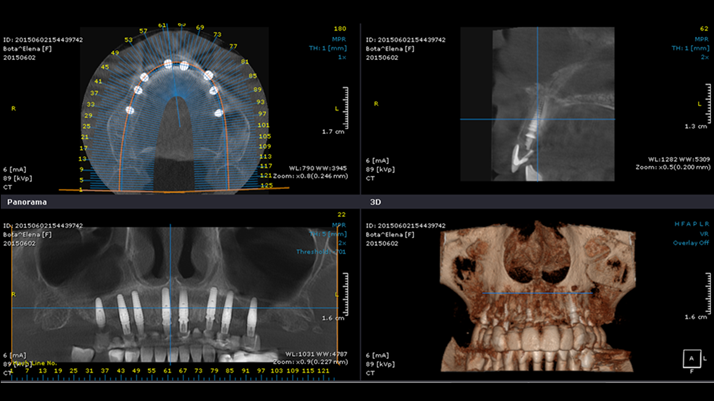

Clinical case: Extraction of all teeth in upper maxilla,

immediate implant placement, & provisionalization

- Courtesy of Dr. Iulian Filipov, Romania -

Keywords

AnyRidge, immediate placement, immediate provisionalization, maxillary fully edentulous case, initial stability, edentulous, Dr. Iulian Filipov, R2GATE, MEGA ISQ

Products:

AnyRidge implant system, Mega ISQ, R2GATE